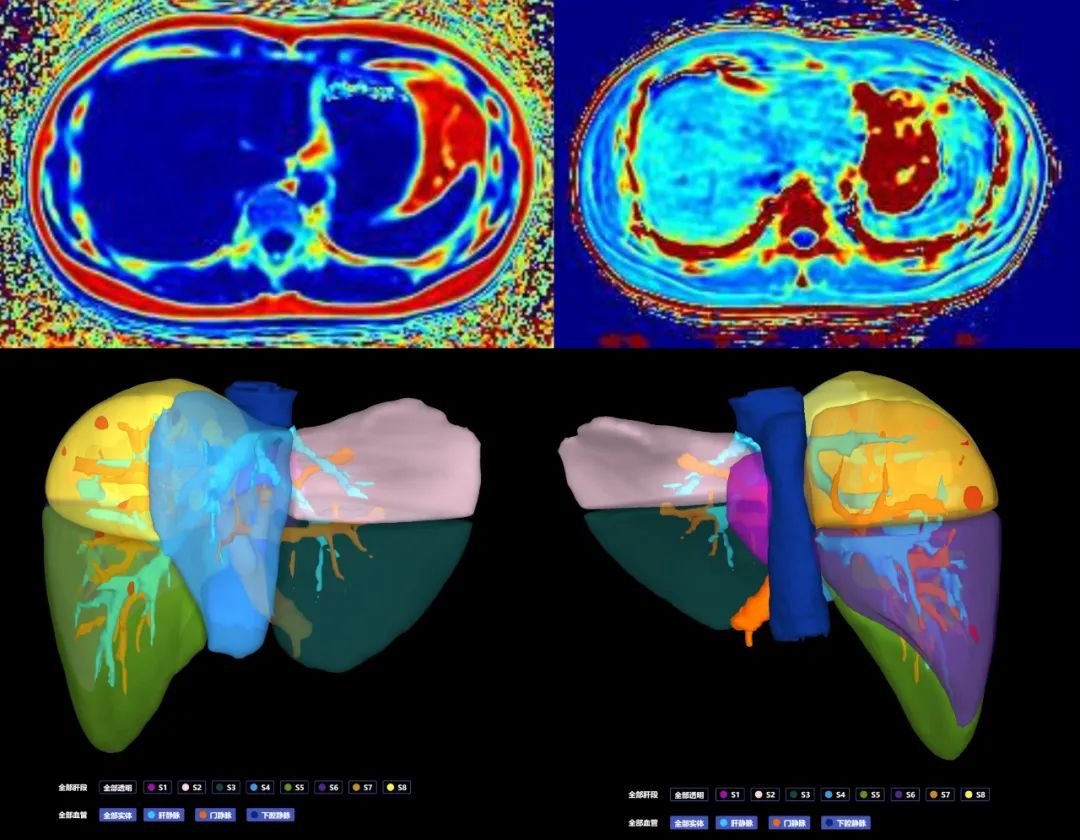

(三)肺結(jié)節(jié)三維可視化重建CT檢查,可結(jié)合原始軸位圖像清晰顯示肺結(jié)節(jié)與周圍毗鄰關(guān)系,尤其是與周圍動靜脈血管的解剖關(guān)系,指導(dǎo)臨床手術(shù)方式的抉擇。

圖片

肺結(jié)節(jié)三維可視化重建CT檢查